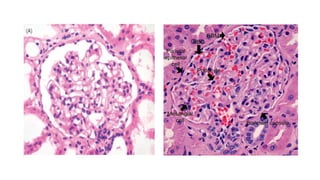

Endocapillary

Hypercellularity

An increased number of cell

within glomerular capillary

lumina.

These may be endothelia cells or

intravascular leucocytes.

(H&E) Post-infectious glomerulonephritis showing

endocapillary hypercellularity, in which the

capillary lumina are filled with infiltrating

leucocytes